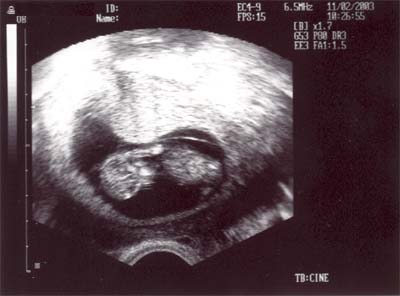

Jetzt in der 11.SSW sehe ich schon aus wie ein Baby, nicht mehr wie ein Pünktchen.

Das Ultraschallbild von Pünktchen.

Es ist jetzt schon 49,7mm gross - eigendlich kein Pünktchen mehr -

und sieht schon aus wie ein Baby - staun -